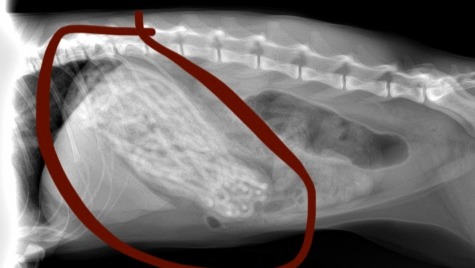

Recently, I noticed that Luna had been eating far less and vomiting for the past week and a half or so, but I was alarmed today (January 5, 2022) when I saw that she had vomited up half of a hair tie. Naturally, I immediately took her to the vet where they did a body exam and some scans. When they showed me the X-Rays (attached in photos), my heart immediately dropped. Luna's stomach was completely filled with black hair ties - the vet expressed that her stomach was so expanded that it would be surprising to him if she could fit anything else in there.

Luna requires an emergency surgery operation (gastrostomy) which they will be performing tomorrow (January 6th, 2022) where they will be opening her stomach to empty the contents and remove the hair ties that are stuck in her stomach. Luckily, the vet told me that these operations are relatively low risk, but her case is unusual in the extent to which her stomach is full, and complications are always possible. Assuming the operation goes well, they will keep her for another two days in the facility to monitor her and ensure she is recovering well.